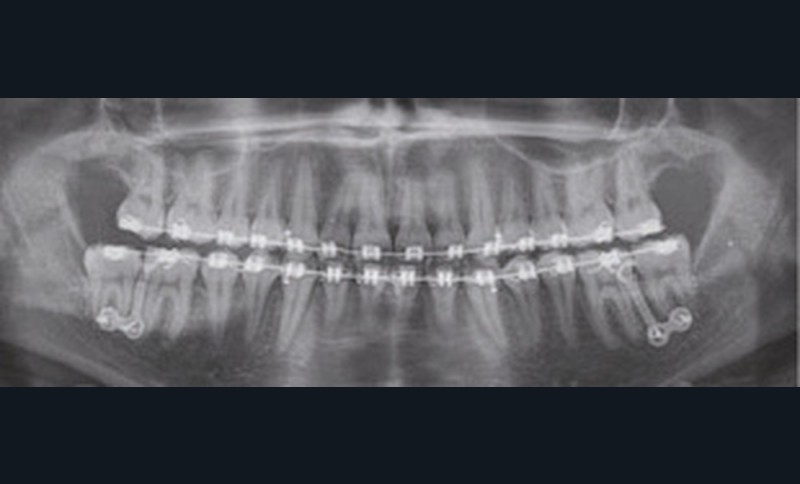

À la vue de l’examen radiographique, elle est au stade CS6 d’après la méthode de maturation vertébrale de Baccetti [1]. Elle présente une classe II squelettique de Ballard par rétrognathie mandibulaire avec un ANB de 9° et un AoBo de 9 mm sur un schéma facial normo-divergent. L’incisive mandibulaire est vestibulo-versée (IMPA = 114°). Le maxillaire est bien positionné. Elle présente de plus une dysharmonie dento-dentaire (DDD) antérieure par excès mandibulaire.

Nous équipons la patiente avec un appareil multi-attaches (.022 x .028 inch pré-informé Roth) mais nous n’avons pas activé l’arcade mandibulaire. La patiente est adressée au chirurgien maxillo-facial (Dr Gonzague Deffrennes, hôpital Beaujon) qui réalise l’avulsion des troisièmes molaires et la pose de plaques vissées avec émergence entre les premières et deuxièmes molaires mandibulaires dans l’axe des brackets (fig. 9). Étant donné l’absence d’encombrement au niveau incisif mandibulaire, nous pouvons rapidement mettre en place les tractions postérieures. Nous solidarisons ainsi le bloc antérieur de canine à canine et réalisons un recul en masse de l’arcade directement des canines aux plaques postérieures. La majeure partie du recul est faite sur un arc acier .018x.025 inch permettant le glissement. La force appliquée est de 250-300 g par côté.

Nous avons pu repositionner l’incisive mandibulaire de 8° (fig. 10), obtenir un surplomb correspondant à la classe II d’Angle et ainsi réaliser l’avancée mandibulaire. Le chirurgien accompagne celle-ci d’une génioplastie afin d’harmoniser le profil. Nous corrigeons la DDD par stripping des incisives mandibulaires ce qui permet de corriger encore de 1° l’axe incisif.